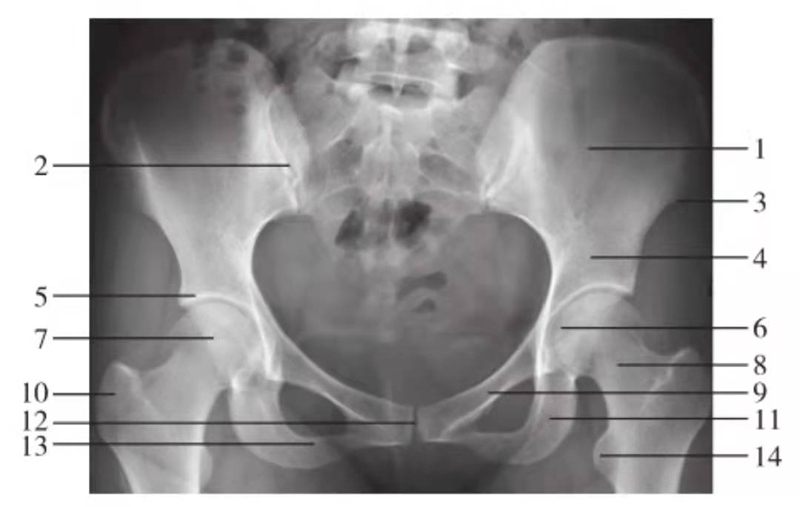

骨盆前后位

骨盆入口位

图7 骨盆入口位

1.骶骨;2.骶髂关节;3.髂骨翼;4.尾骨;5.坐骨棘;6.股骨头;7.耻骨上支;8.坐骨支;9.耻骨联合

骨盆出口位

图8 骨盆出口位

1.髂骨翼;2.骶髂关节;3.骶骨;4.耻骨上支;5.耻骨联合;6.股骨颈;7.坐骨支;8.尾骨;9.耻骨下支